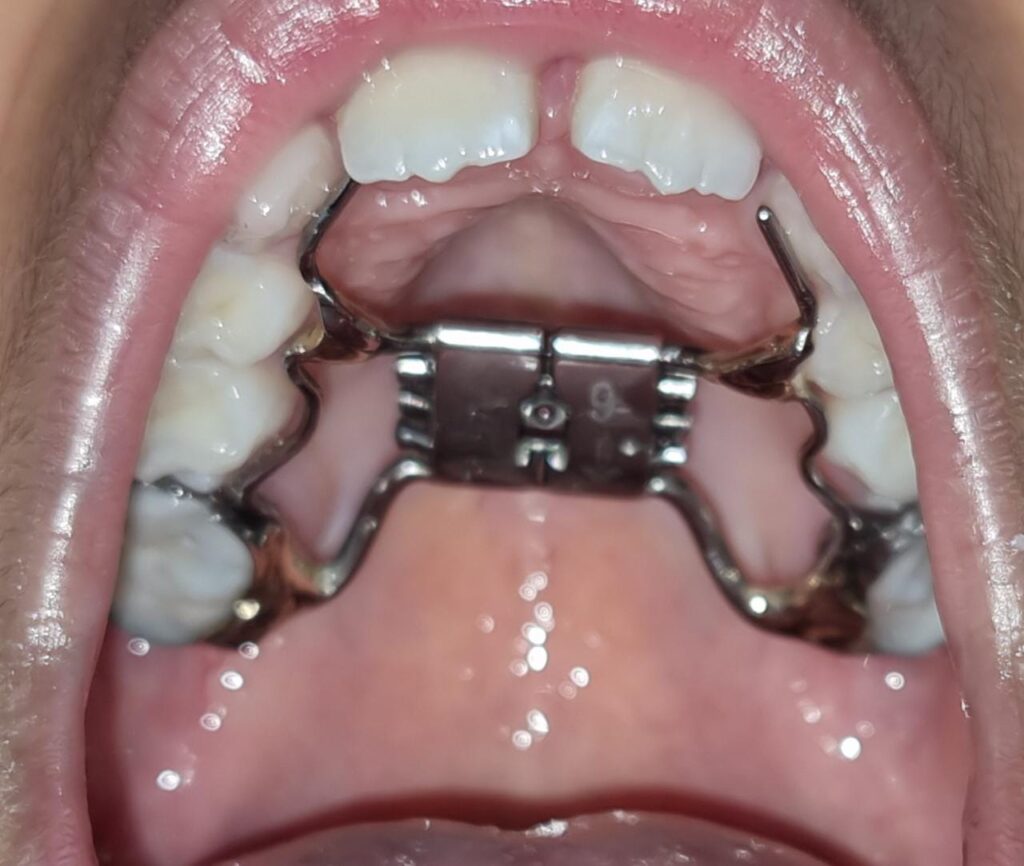

76) Ayyan – Tongue thrust